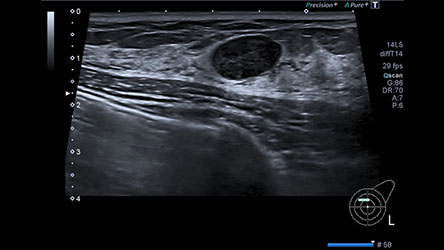

Ultraschall

- Brustultraschall inklusive Elastographie

- Axillaultraschall